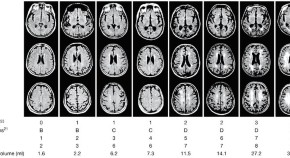

• Baló's concentric sclerosis (BCS) is a demyelinating disorder characterized by white matter lesions consisting of rings of demyelination alternating with rings of relatively intact myelin. In this Review, Mowryet al.discuss how advanced neuroimaging techniques have contributed to our understanding of the pathogenesis of BCS, as well as enabling clinicians to distinguish BCS from other demyelinating disorders such as multiple sclerosis. The authors explore these themes further in a Case Study in this issue.

• Ellen M Mowry

• John H Woo

• Beau M Ances